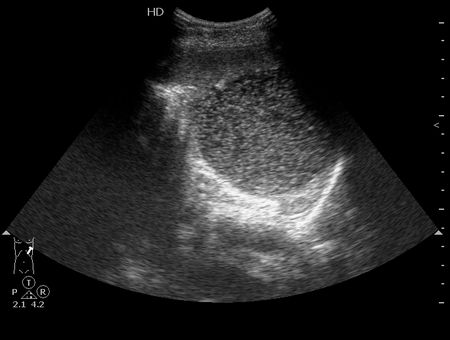

Удивительно, но факт - вчера к нам поступила такая-же "селезенка".

В нашем случае - это кистозное образование - при изменении положения тела происходит перемешивание жидкости внутри

В анамнезе у девушки была травма и перелом поясничного позвонка.